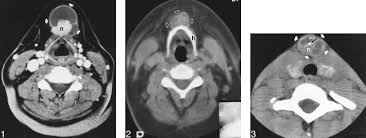

Cáncer Papilar de Tiroides en el Conducto Tirogloso

Los restos del conducto tirogloso son comunes, comprenden más del 75% de los tumores de cuello de línea la media en niños y 7% en adultos, aunque es raro encontrar un cáncer dentro de uno de estos quistes.

En un estudio grande se reportó una prevalencia de cáncer en el 1.3% de los remanentes del conducto tirogloso:

• El cáncer papilar es el tumor más común (90% de los casos)

• La mayoría mide menos de 1 cm

• Por lo general, están confinados al quiste